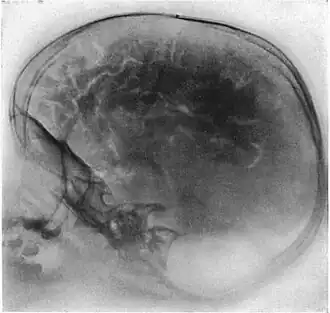

Pneumoencephalography (sometimes abbreviated PEG; also referred to as an "air study") was a common medical procedure in which most of the cerebrospinal fluid (CSF) was drained from around the brain by means of a lumbar puncture and replaced with air, oxygen, or helium to allow the structure of the brain to show up more clearly on an X-ray image. It was derived from ventriculography, an earlier and more primitive method in which the air is injected through holes drilled in the skull.

Pneumoencephalography makes use of plain X-ray images. These are very poor at resolving soft tissues, such as the brain. Moreover, all the structures captured in the image are superimposed on top of each other, which makes it difficult to pick out individual items of interest (unlike modern scanners, which are able to produce fine virtual slices of the body, including of soft tissues). Therefore, pneumoencephalography did not usually image abnormalities directly; rather, their secondary effects. The overall structure of the brain contains crevices and cavities that are filled by the CSF. Both the brain and the CSF produce similar signals on an X-ray image. However, draining the CSF allows for greater contrast between the brain matter and the (now drained) crevices in and around it, which then show up as dark shadows on the X-ray image. The aim of pneumoencephalography is to outline these shadow-forming air-filled structures so that their shape and anatomical location can be examined. Following the procedure, an experienced radiologist reviews the X-ray films to see if the shape or location of these structures have been distorted or shifted by the presence of certain kinds of lesions. This also means that in order to show up on the images, lesions have to either be located right on the edge of the structures or if located elsewhere in the brain, be large enough to push on surrounding healthy tissues to an extent necessary to cause a distortion in the shape of the more distant air-filled cavities (and hence more-distant tumors detected this way tended to be fairly large).